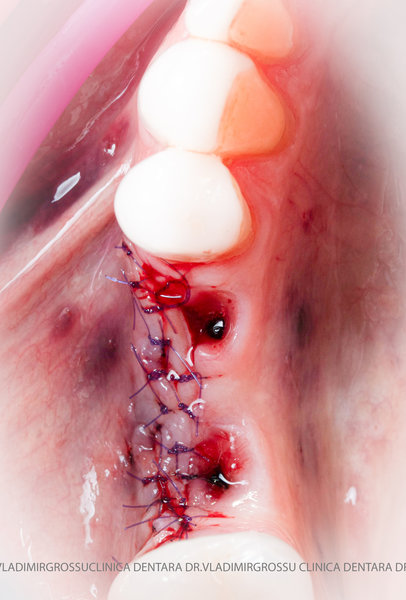

Un element esențial în procedura de aditie osoasă este utilizarea membranelor biologice, care izolează materialul osos de țesuturile moi (gingie) pe durata procesului de vindecare. Cele mai recomandate sunt membranele resorbabile din colagen sau pericard.

Adiția de gingie (gingivoplastia)

Aditia gingivală este o procedură chirurgicală ce corectează diverse probleme estetice și funcționale, cum ar fi recesiunea gingivală. În implantologia modernă, aditia de țesut moale este utilizată aproape în fiecare intervenție de inserție a implantului dentar pentru a asigura un aspect estetic natural și o bună integrare a implantului în cavitatea bucală.